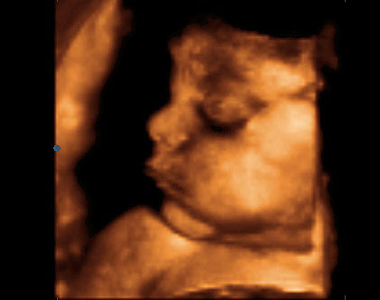

Druhý trimestr (14. týden těhotenství až 27. týden těhotenství)

Nejvýznamnějším v tomto období jsou pohyby plodu, které matka začne cítit kolem 20. týdne těhotenství, druho a vícerodička již kolem 18. týdne těhotenství. Jedná se o období rychlého růstu plodu a vývoje orgánů. Komplikace jako nevolnost začínají ustupovat, naopak se objevují ty, které souvisí se zvětšující se velikostí plodu.